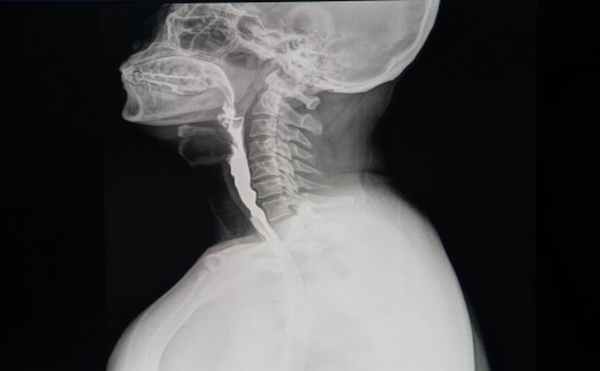

Пищевод начинается позади перстневидного хряща и представляет собой пищепроводную трубку, сплюснутую спереди назад и имеющую длину 24—28 см у мужчин и 21—23 см у женщин. Она расположена непосредственно перед позвоночником — между VI—VII шейными и X—XI грудными позвонками. На протяжении имеются три физиологических сужения: в начале пищевода (обусловлено нижним сжимателем глотки); в грудной части пищевода приблизительно на середине его длины (образовано сдавлением аортой и левым бронхом); в начале брюшной части пищевода (в месте его прохождения через диафрагму).

В грудной части пищевод задней стенкой прилежит к позвоночному столбу, передней стенкой — к бифуркации трахеи, правой — к левому главному бронху, левой — к средостению. На уровне IV грудного позвонка вблизи пищевода находятся грудной лимфатический проток, левые подключичная артерия и возвратный нерв, дуга аорты, а в области VIII—IX грудных позвонков — нисходящая часть дуги аорты, грудной лимфатический проток, межреберные артерии, непарная и полунепарная вены, левое предсердие, средостенная плевра, паратрахеальные лимфатические узлы. Брюшная часть пищевода задней поверхностью прилежит к лгвой ножке диафрагмы, а передней — к печени.

При воспалительных процессах в мягких тканях их толщина увеличивается и пищевод как бы отделяется либо от позвоночника, либо от трахеи. При травматических повреждениях слизистой оболочки пищевода на боковых рентгенограммах шеи отмечается характерное просветление с четкими ровными контурами — скопление воздуха (симптом «воздушной стрелки»), что связано с воспалительным отеком травмированной слизистой оболочки пищевода, сужением его просвета и задержкой воздуха, выходящего из желудка.